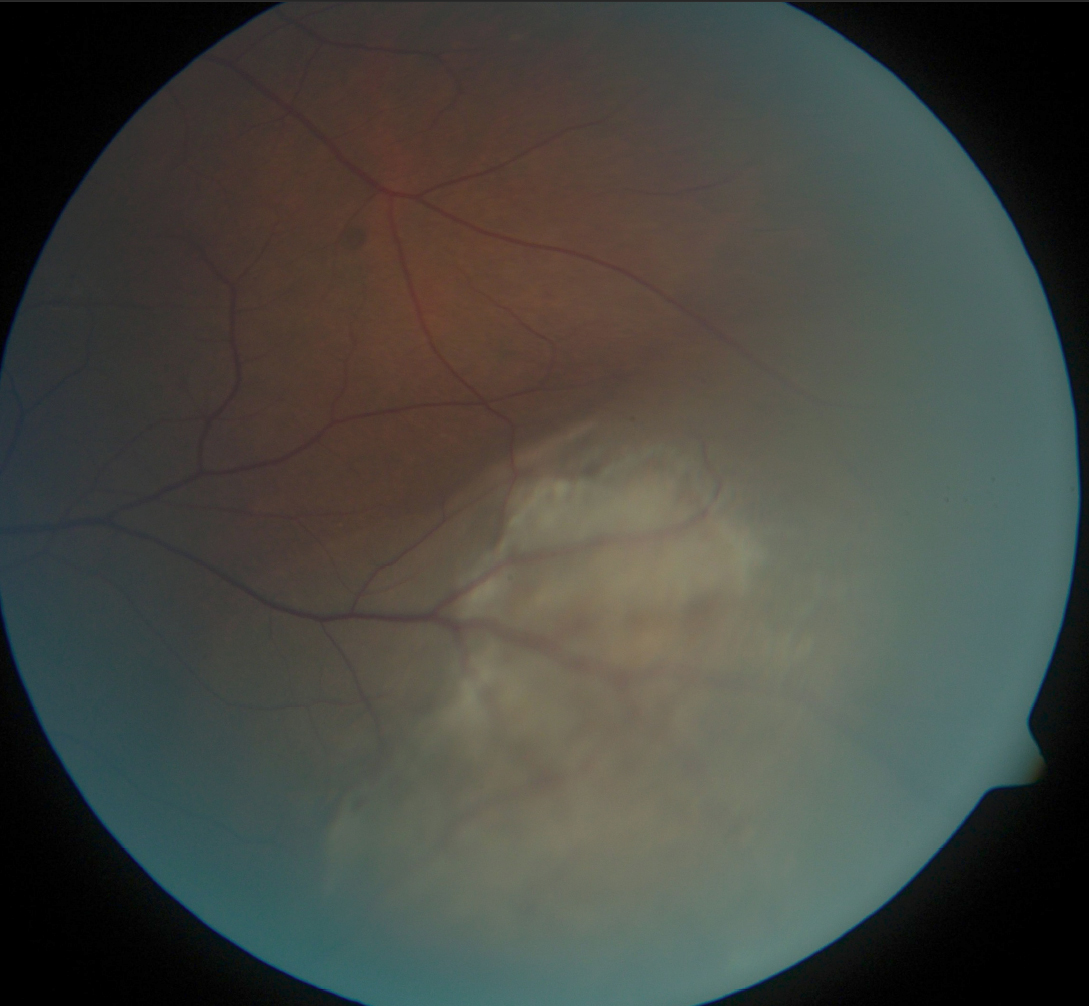

Figure 4 of McCannel, Mol Vis 2011; 17:231-236.

Figure 4. Color fundus photograph of the left eye in Case 3 at initial presentation demonstrates an inferotemporal choroidal melanoma.